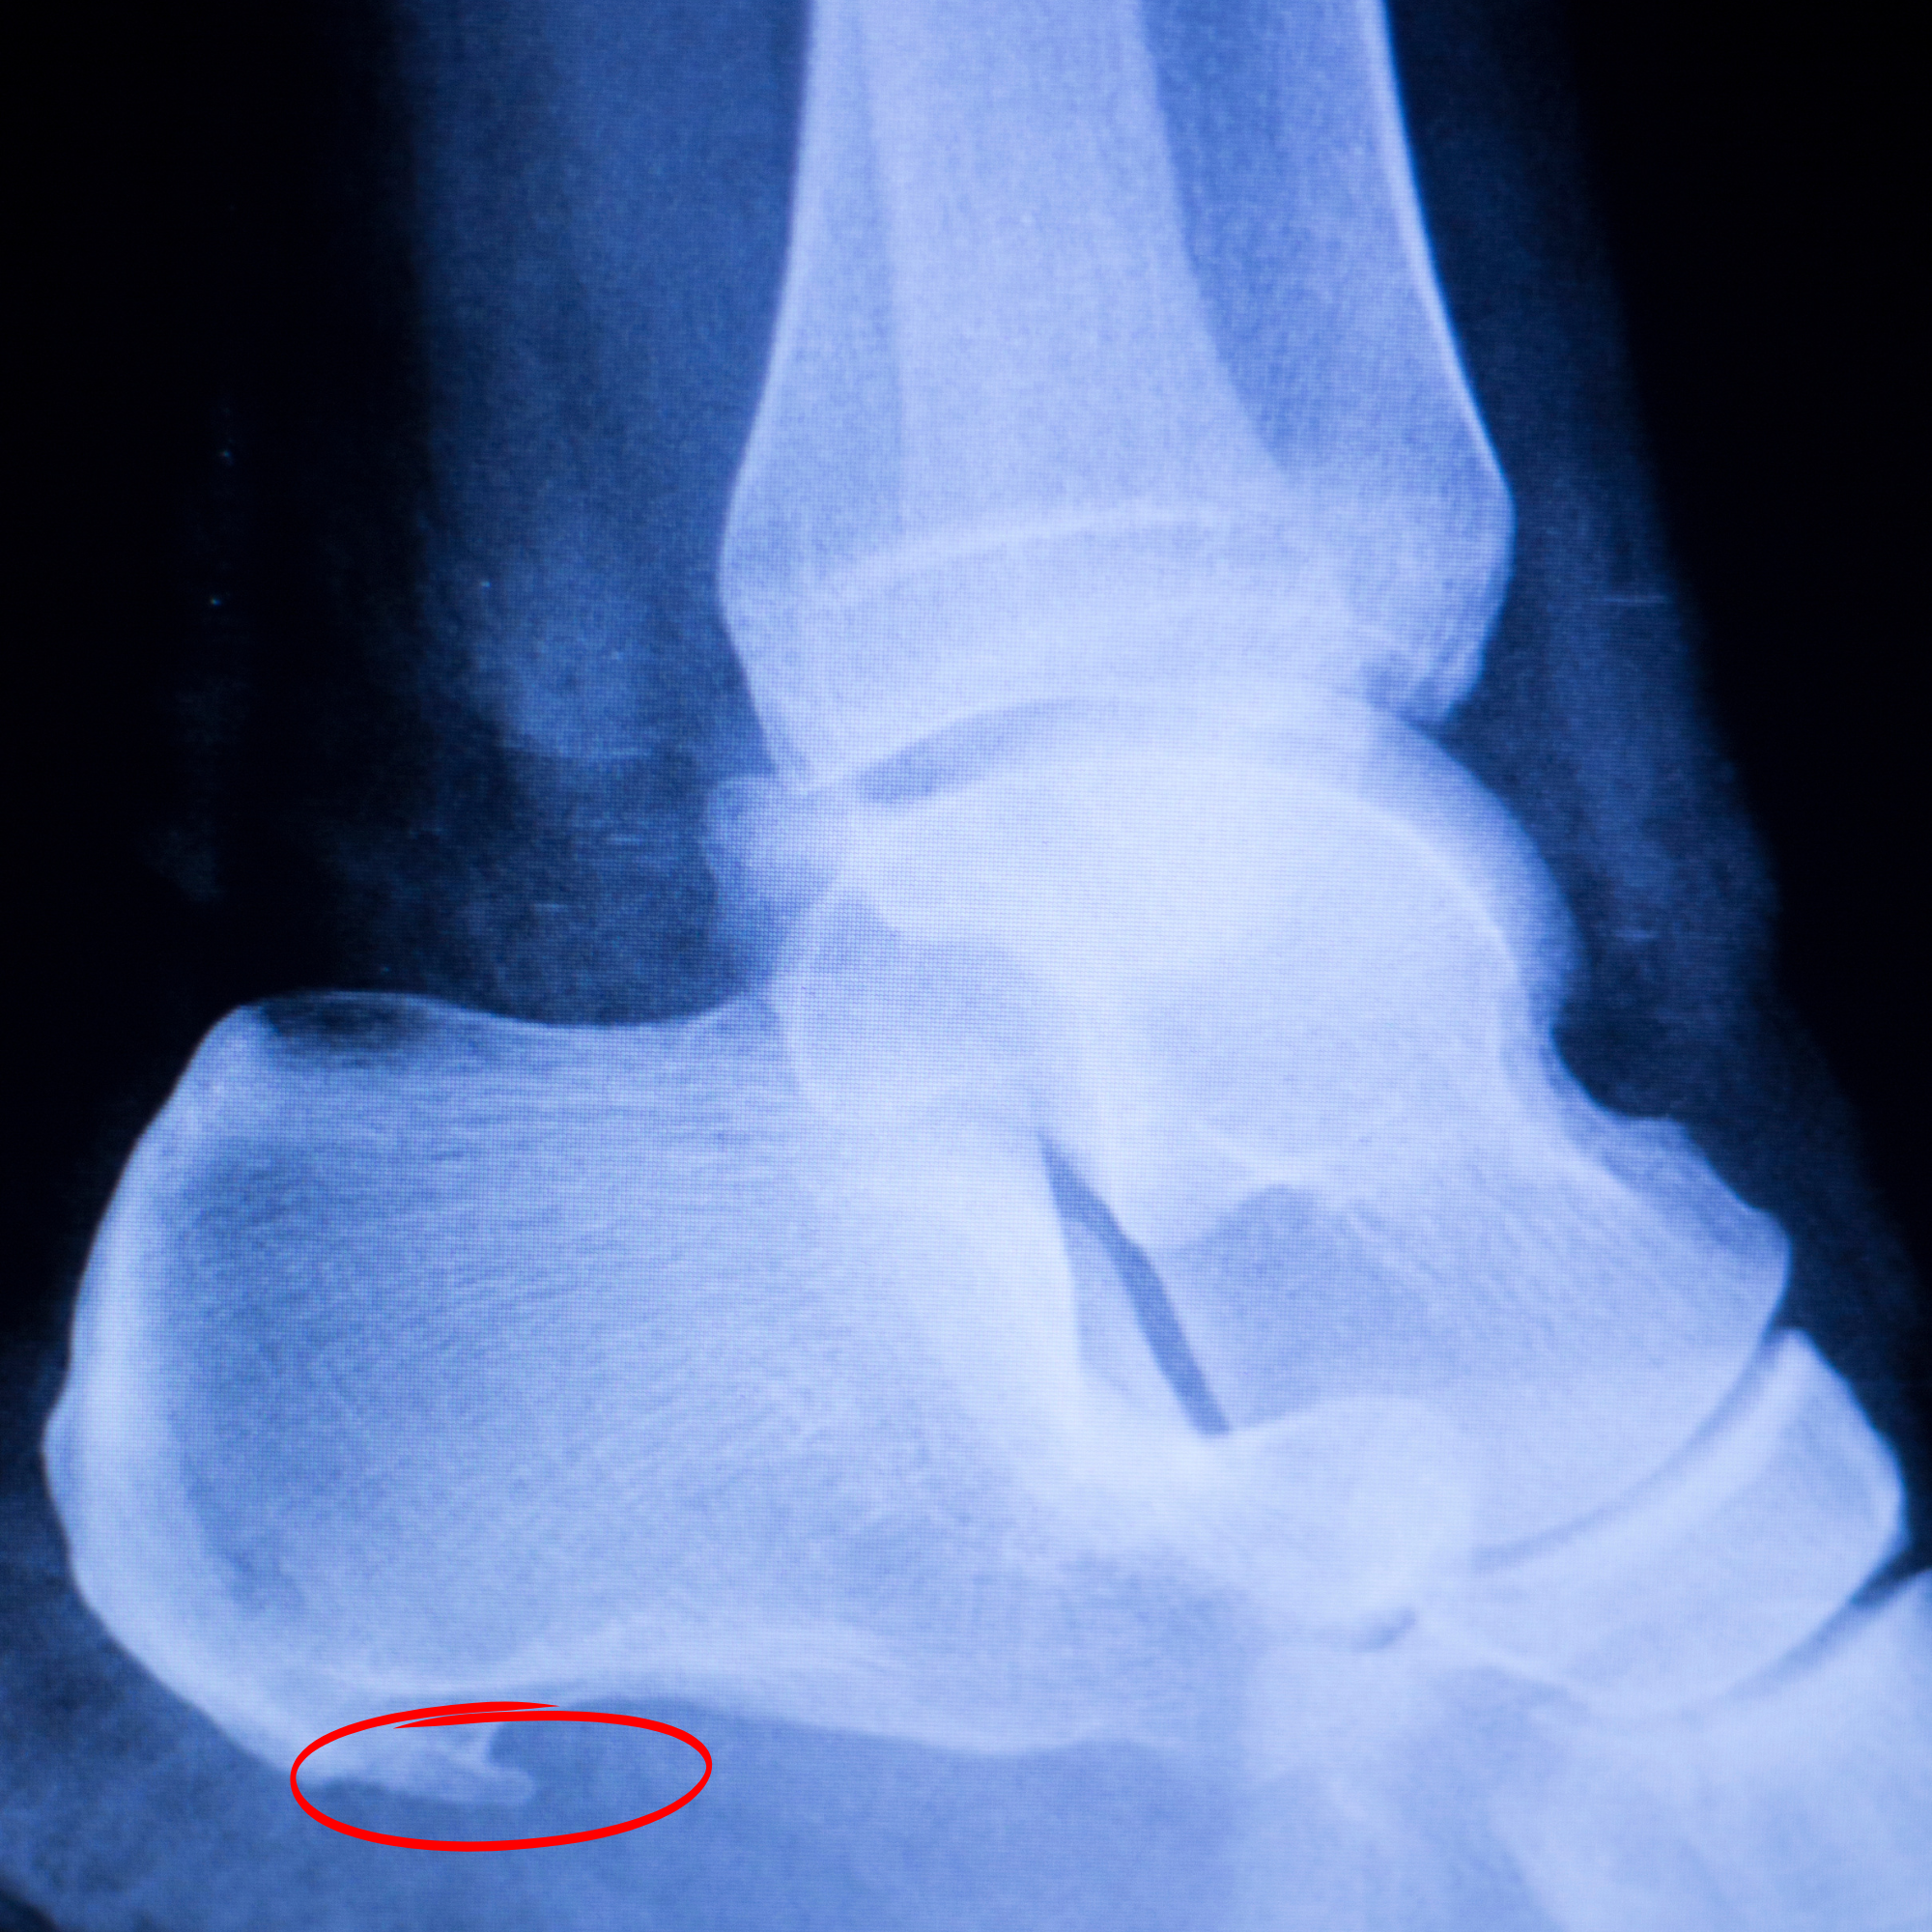

Have you ever been told you have a bone spur in your heel ? Did that make you worry about that bone spur and make you want it taken out surgically? Does that bone spur matter? H...